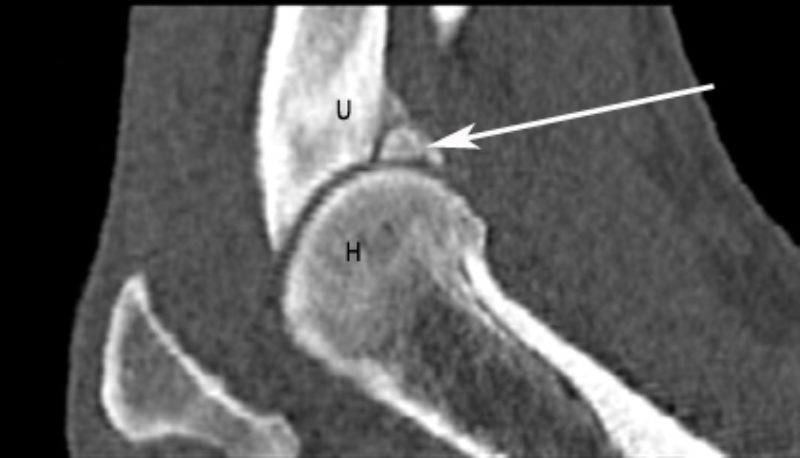

Nachdem ich bei „Oscar“ die Narkosefähigkeit geprüft hatte, haben wir einen Venenkatheter eingelegt und darüber die Narkose eingeleitet. „Oscar“ bekam einen Luftröhrentubus, damit in der Narkose die Atmung nicht behindert wird und er Narkosegase einatmen kann. „Oscar“ wurde für die Untersuchung der Ellbogengelenke in Brustlage mit gestreckten Vordergliedmaßen auf dem Untersuchungstisch gelagert und mit kontrastarmen Lagerungshilfen (z.B. Schaumstoffkeile oder Rohrisolationen) positioniert. Die reine Untersuchungszeit im CT beträgt für eine Ellbogensequenz ca. 10-15 Sekunden (120 kV, 200 mAs, Schichtdicke 0,75 mm, W 2500 L 500, Ellbogen beidseits transversal, nativ). Bei „Oscar“ fand ich auf diese Weise einen feinen Riss am inneren Kronfortsatz der Elle (Processus coronoideus medialis ulnae). Seine eigentliche Spitze war durch Entmineralisation bereits weniger röntgendicht. Als Folge dieses „Bruches“ war es zu einer Reizung des Gelenks und damit zu einer beginnenden Arthrose mit Ausbildung von Knochenspikes gekommen.

Diadnose: Abgebrochener innerer Kronfortsatz

Somit stand die Diagnose „abgebrochener innerer Kronfortsatz“ (fragmentierter Processus coronoideus medialis ulnae) als Ursache für die Lahmheit bei „Oscar“ fest. Diese Erkrankung zählt zum Formenkreis der Ellbogengelenkdysplasie und ist eine der häufigsten Lahmheitsursachen der Vordergliedmaße beim großwüchsigen Hund. Da das Belassen des abgebrochenen Kronfortsatzes die Arthrosebildung begünstigt, haben wir in der gleichen Narkose das Bruchstück arthroskopisch entfernt.